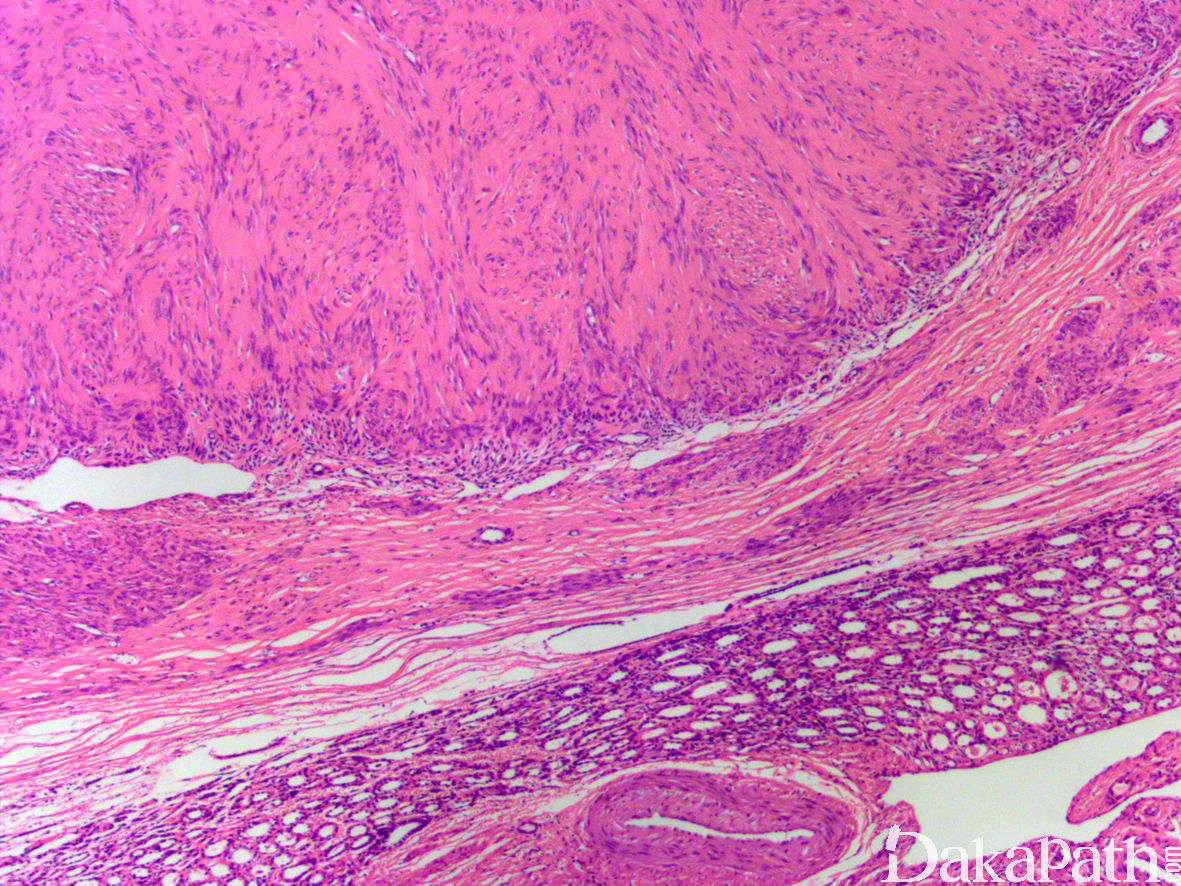

2. 大体上,平滑肌瘤是界限清楚的实性肿瘤,切面呈小梁状,可有钙化和囊性变,但无坏死;

3. 组织形态与发生于后腹膜和子宫部位的平滑肌瘤相同,由梭形细胞交错束状排列构成,也可呈编织状甚至栅栏样排列,间质常见玻璃样和水肿变性;

4. 细胞无异型性和核分裂。